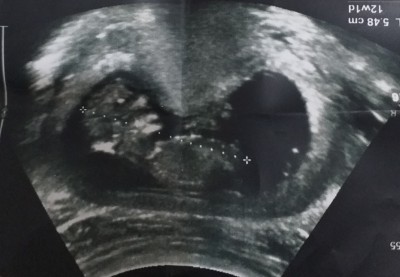

11 . Haftamdayim ikili tarama testi icin gittim ultrason kagidindan anlayan varmi sizce nedir

Gebelik haftası 11